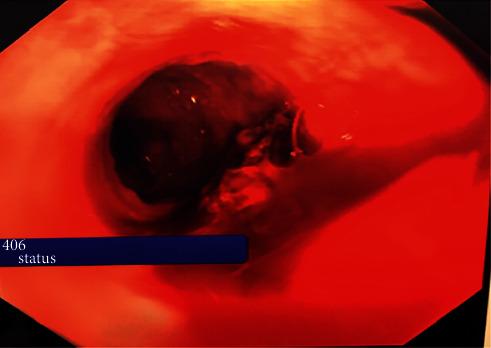

A 35-year-old gentleman presented acutely to the emergency department with large volume haematemesis and melena. Following adequate initial resuscitation, the patient underwent emergency upper gastrointestinal endoscopy which revealed a dilated tortuous submucosal vessel which was actively bleeding at the midpoint of the esophagus. This was consistent with a Dieulafoy lesion. However, its position in the midpoint of the esophagus is rare. Our patient recovered well following intervention.

一名35岁男性因大量呕血和黑便急症就诊于急诊科。经过充分的初始复苏后,患者接受了急诊上消化道内镜检查,结果显示食管中段有一条扩张迂曲的黏膜下血管正在活动性出血。这符合迪厄拉富瓦病损表现。然而,其位于食管中段的情况较为罕见。我们的患者经干预后恢复良好。